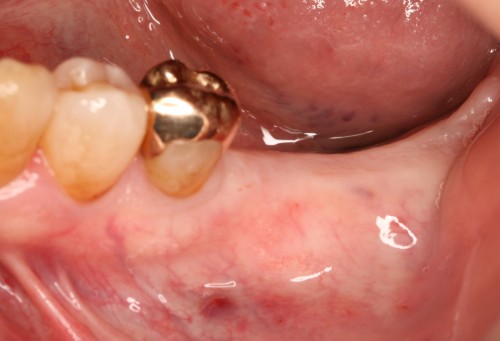

インプラント 右上4567 川口で精密インプラントなら さかえ歯科